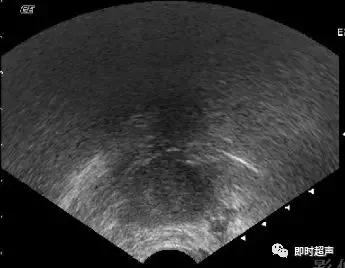

单纯性囊肿:卵泡囊肿、黄体囊肿、附件炎性囊肿、卵巢冠囊肿、阔韧带囊肿等,可通称为单纯性囊肿。一般内部透声好,无明显光点,超声表现为宫旁附件区囊性肿物,壁薄,内无回声。而卵巢畸胎瘤表现为单房状瘤内无回声时,可见囊壁局限性增厚,伴回声增强。